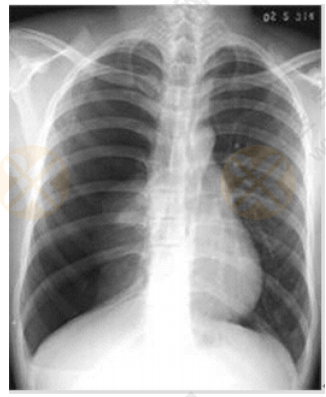

根據(jù)下圖所給X線片分析臨床意義。(5分)